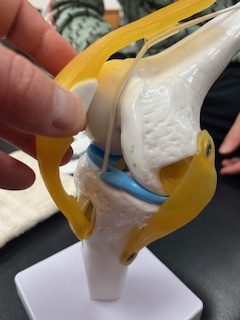

今回のテーマは「膝」 待ってました! 一番興味がある部位ですね

今回のテーマは「膝」 待ってました! 一番興味がある部位ですね